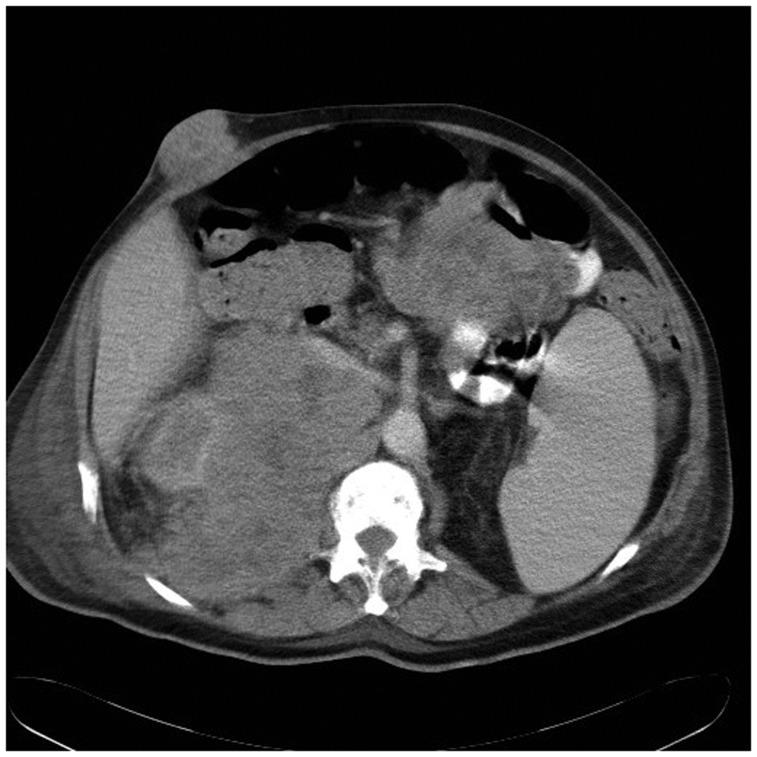

The mean latency from the primary tumor diagnosis to systemic metastasis was 2.1 years and the mean latency between the radiologic diagnosis of the metastases and death was 299 days. Metastases were recorded in several organ systems in most of the cases, and at least two separate metastatic sites in 63% of the cases. Metastatic spread was noted in 60% of the cases in distant lymph nodes. Liver and lungs were the most affected solid organs.

结果

从原发性肿瘤诊断到全身转移的平均间隔时间为2.1年,转移灶的影像学诊断与死亡之间的平均间隔时间为299天。大多数病例在多个器官系统中记录到转移,63%的病例至少有两个独立的转移部位。60%的病例出现远处淋巴结转移。肝脏和肺是受影响最严重的实体器官。